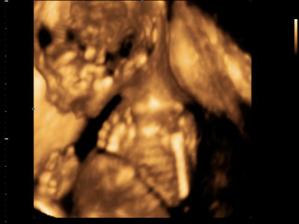

Terezka

Terezka se nám narodila 12.7.2007, měla 50cm a 3100 kg, dnes už je z ní pěkná 2 letá holčička